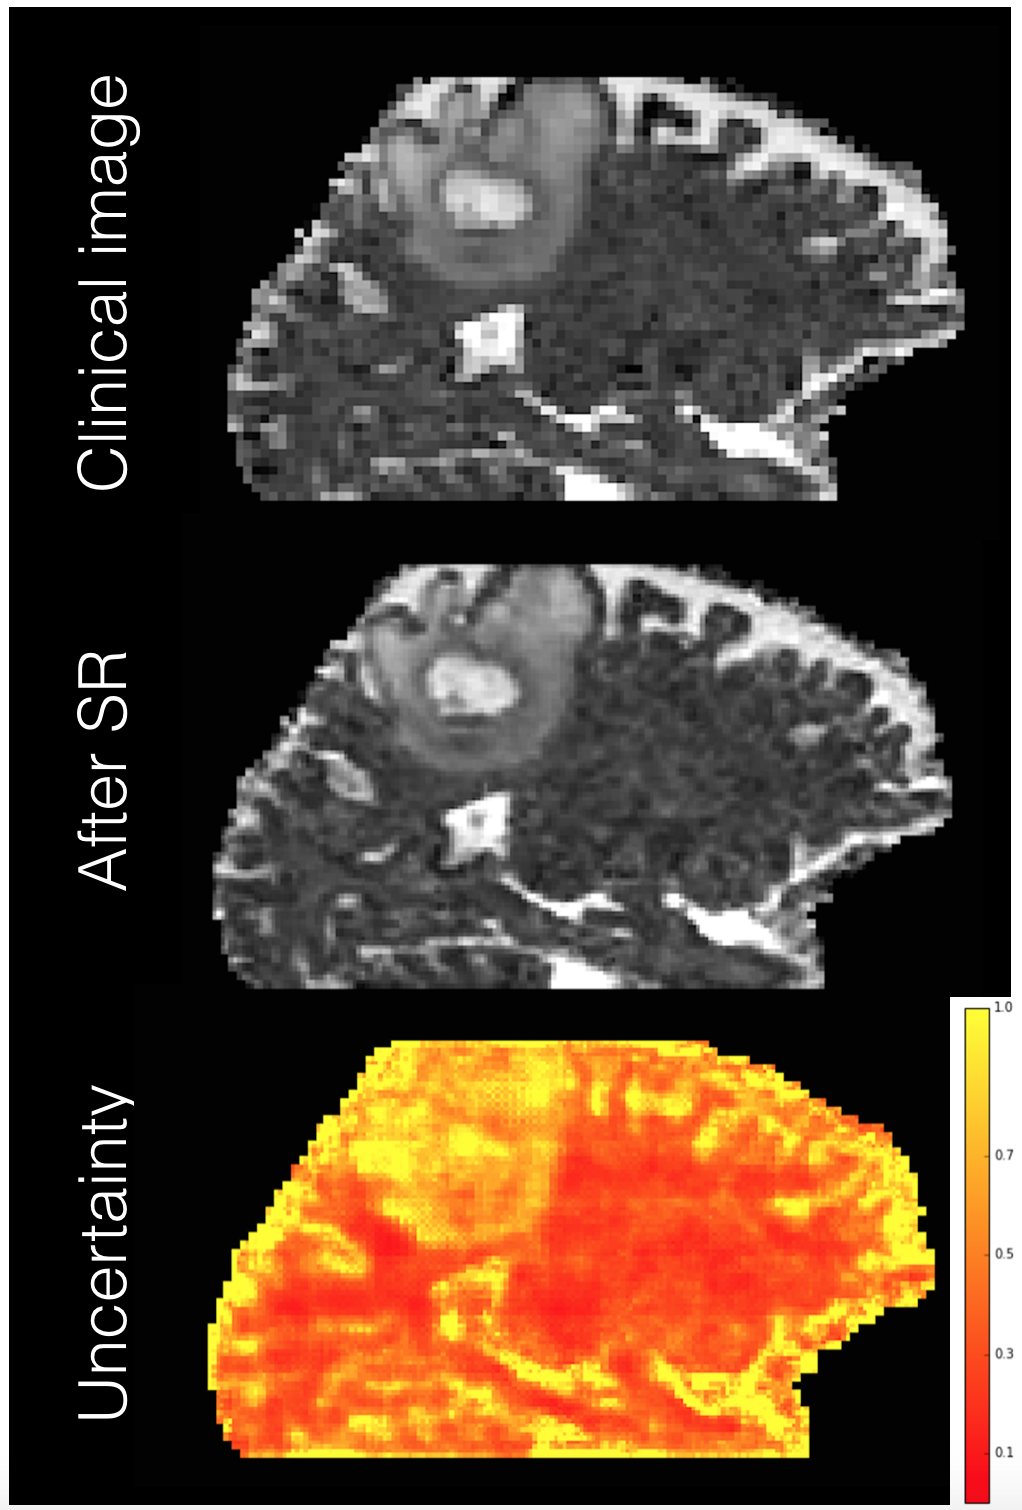

Refer to caption

Fig. 5(b) shows the best-performing SR model (Hetero+Var (II)) trained on a healthy HCP cohort applied to the DTI of a brain tumour patient. The raw data (DWI) with b=700 s/mm2𝑏700superscript s/mm2b=700\text{ s/mm}^{2} is processed as before with input voxel size 23 mm3superscript23superscript mm32^{3}\text{ mm}^{3}. We show the input, SR image and uncertainty map. The ground truth is unavailable but the estimated image sharpens the input without introducing noticeable artifacts. The uncertainty map shows high uncertainty on the tumour, not represented in the training data, again illustrating the potential of the uncertainty maps to flag potential low accuracy areas.